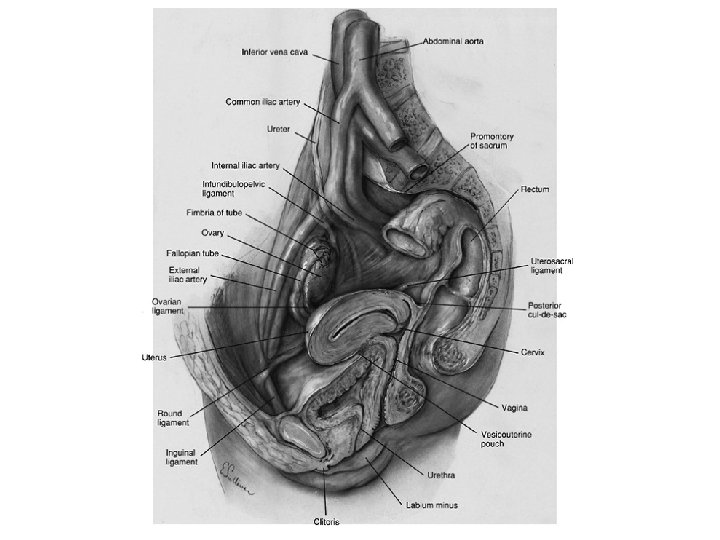

Ovaries Medulla (blood and lenf vessels, nerves) Cortex (germinal epitel, tunica albuginea, hilum ovarii) Lig. Ovarii Proprium (between overies and uterus) Lig. Suspensorium Ovarii (infundibulopelvic) (between overies and pelvic side wall) • A. ovarica, plexus pampiniformis • •

• Ovarian arteries – Originate directly from the aorta, inferior to the renal arteries. – Most frequently identified at the IP ligament. • Ovarian veins: – Left ovarian vein drains into the left renal vein – Right ovarian vein drains directly into the inferior vena cava.

Ligaments of the Uterus • Lig. Sacrouterinum (LUNA) • Lig. Latum Uteri • Lig. Rotundum – Cyst of Nuck canal – A. Sampson – Lig. Cardinale most important lig.